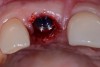

Fig 17. Piezosurgery was used for a minimally invasive extraction that did not damage the soft tissues.

Figure 17